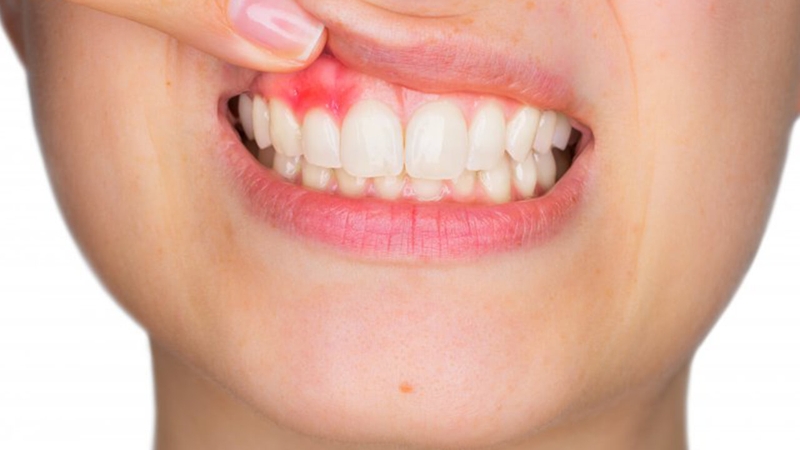

Ở giai đoạn này, bệnh rất khó phát hiện vì người bệnh sẽ có biểu hiện giống như nhiệt miệng, viêm lợi. Trên niêm mạc miệng của bệnh nhân sẽ xuất hiện các vết loét có màu đỏ hoặc trắng, gây đau đớn và chảy máu. Vết loét lâu lành hơn bình thường, có thể kéo dài trên 2 tuần, kèm theo đó là sự thay đổi màu sắc của vùng niêm mạc xung quanh.

/https://cms-prod.s3-sgn09.fptcloud.com/cach_dieu_tri_ung_thu_nuou_rang_2_f648252165.jpg) Ở giai đoạn đầu, ung thư nướu răng rất khó phát hiện

Ở giai đoạn đầu, ung thư nướu răng rất khó phát hiệnGiai đoạn này, người bệnh đã bắt đầu xuất hiện các triệu chứng đặc trưng như: